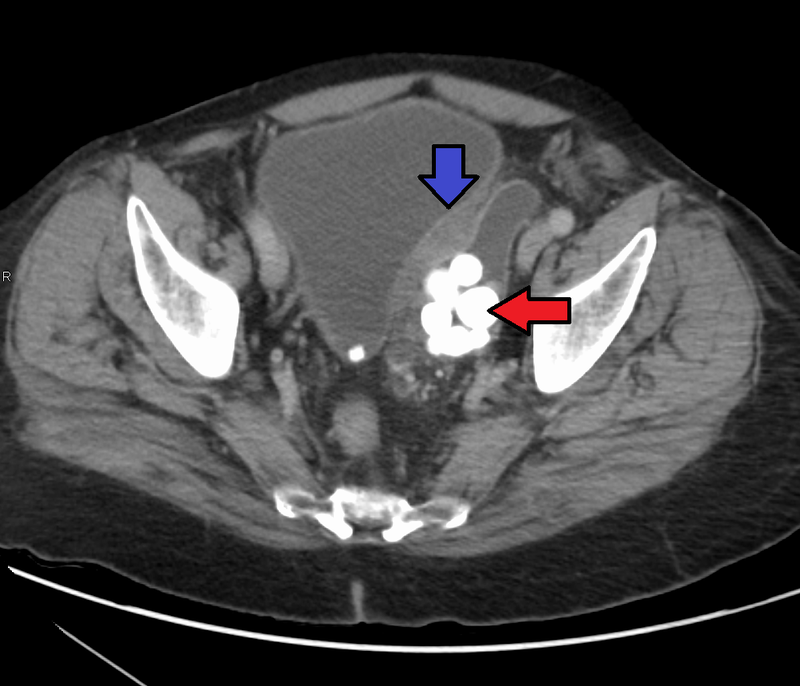

Renal cell carcinoma (RCC) is a malignant cancer cells are located in the lining of kidney tubules, which are incredibly tiny tubes. This condition is known as renal cell carcinoma.

- Hematuria (most common)

- Palpable mass

- Flank pain

Rarely, renal cell carcinoma may present with a left-sided varicocele.

The left spermatic vein cannot drain properly due to cancer in the left renal vein, which causes a varicocele.

Right-sided varicocele is not seen because the right spermatic vein empties straight into the inferior vena cava (IVC).